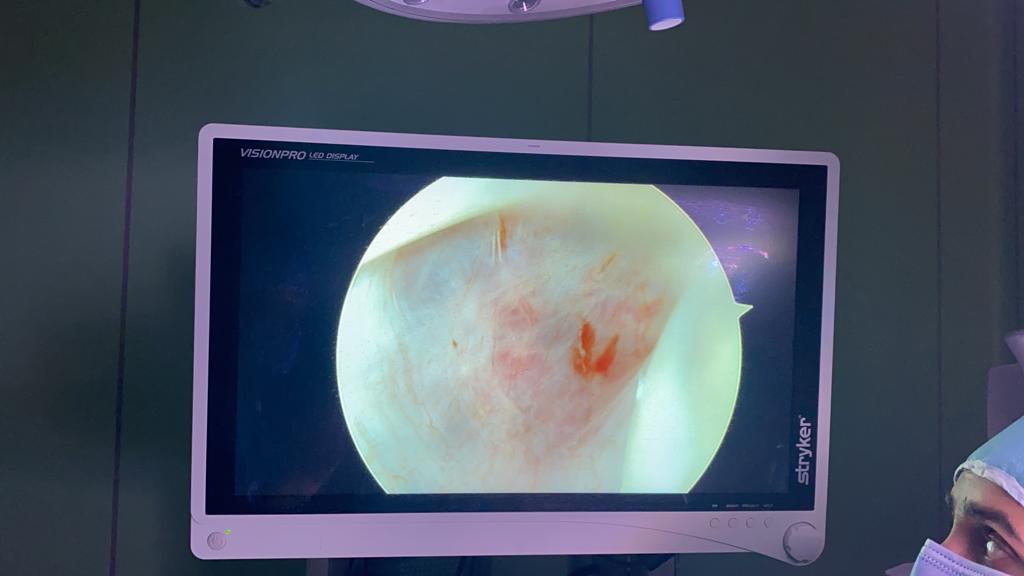

وأوضح الدكتور هاني إمبابي مدير عام مستشفى احمد ماهر التعليمي أن المستشفى نجحت في اجراء قسطرة مخية لا تداخلية لطفلة صغيرة تعاني من ورم دموي كبير متصل بالمخ ووحمة دموية، وتمت العملية على مرحلتين حيث تم عمل قسطرة مخية لفصل الورم تماما وبنجاح، ثم تم عمل استئصال كامل له، والطفلة حالتها مستقرة وتخضع للمتابعة الطبية حاليا.

واضاف أن المستشفى قامت بإستثمار التقنيات الحديثة التى زودت بها مؤخرا، مثل المناظير الحديثة حيث تم تشغيل منظار المخ وتم اجراء عدد 5 حالات لمنظار المخ لحالات الأطفال، كما تم لأول مرة بالمستشفى عمل حالة تصوير بالموجات الصوتية داخل القلب بقسطرة القلب،كما قام قسم جراحة الوجه والفكين باجراء أول جراحة بالمنظار لمفصل الفك بمستشفى الجمهورية التعليمي التابعة للمستشفى باجراء جراحة لحالتين لاستكشاف وغسيل وحقن مفصل الفك بالمنظار معلنا بداية تشغيل خدمات المناظير بقسم جراحة الوجه والفكين.